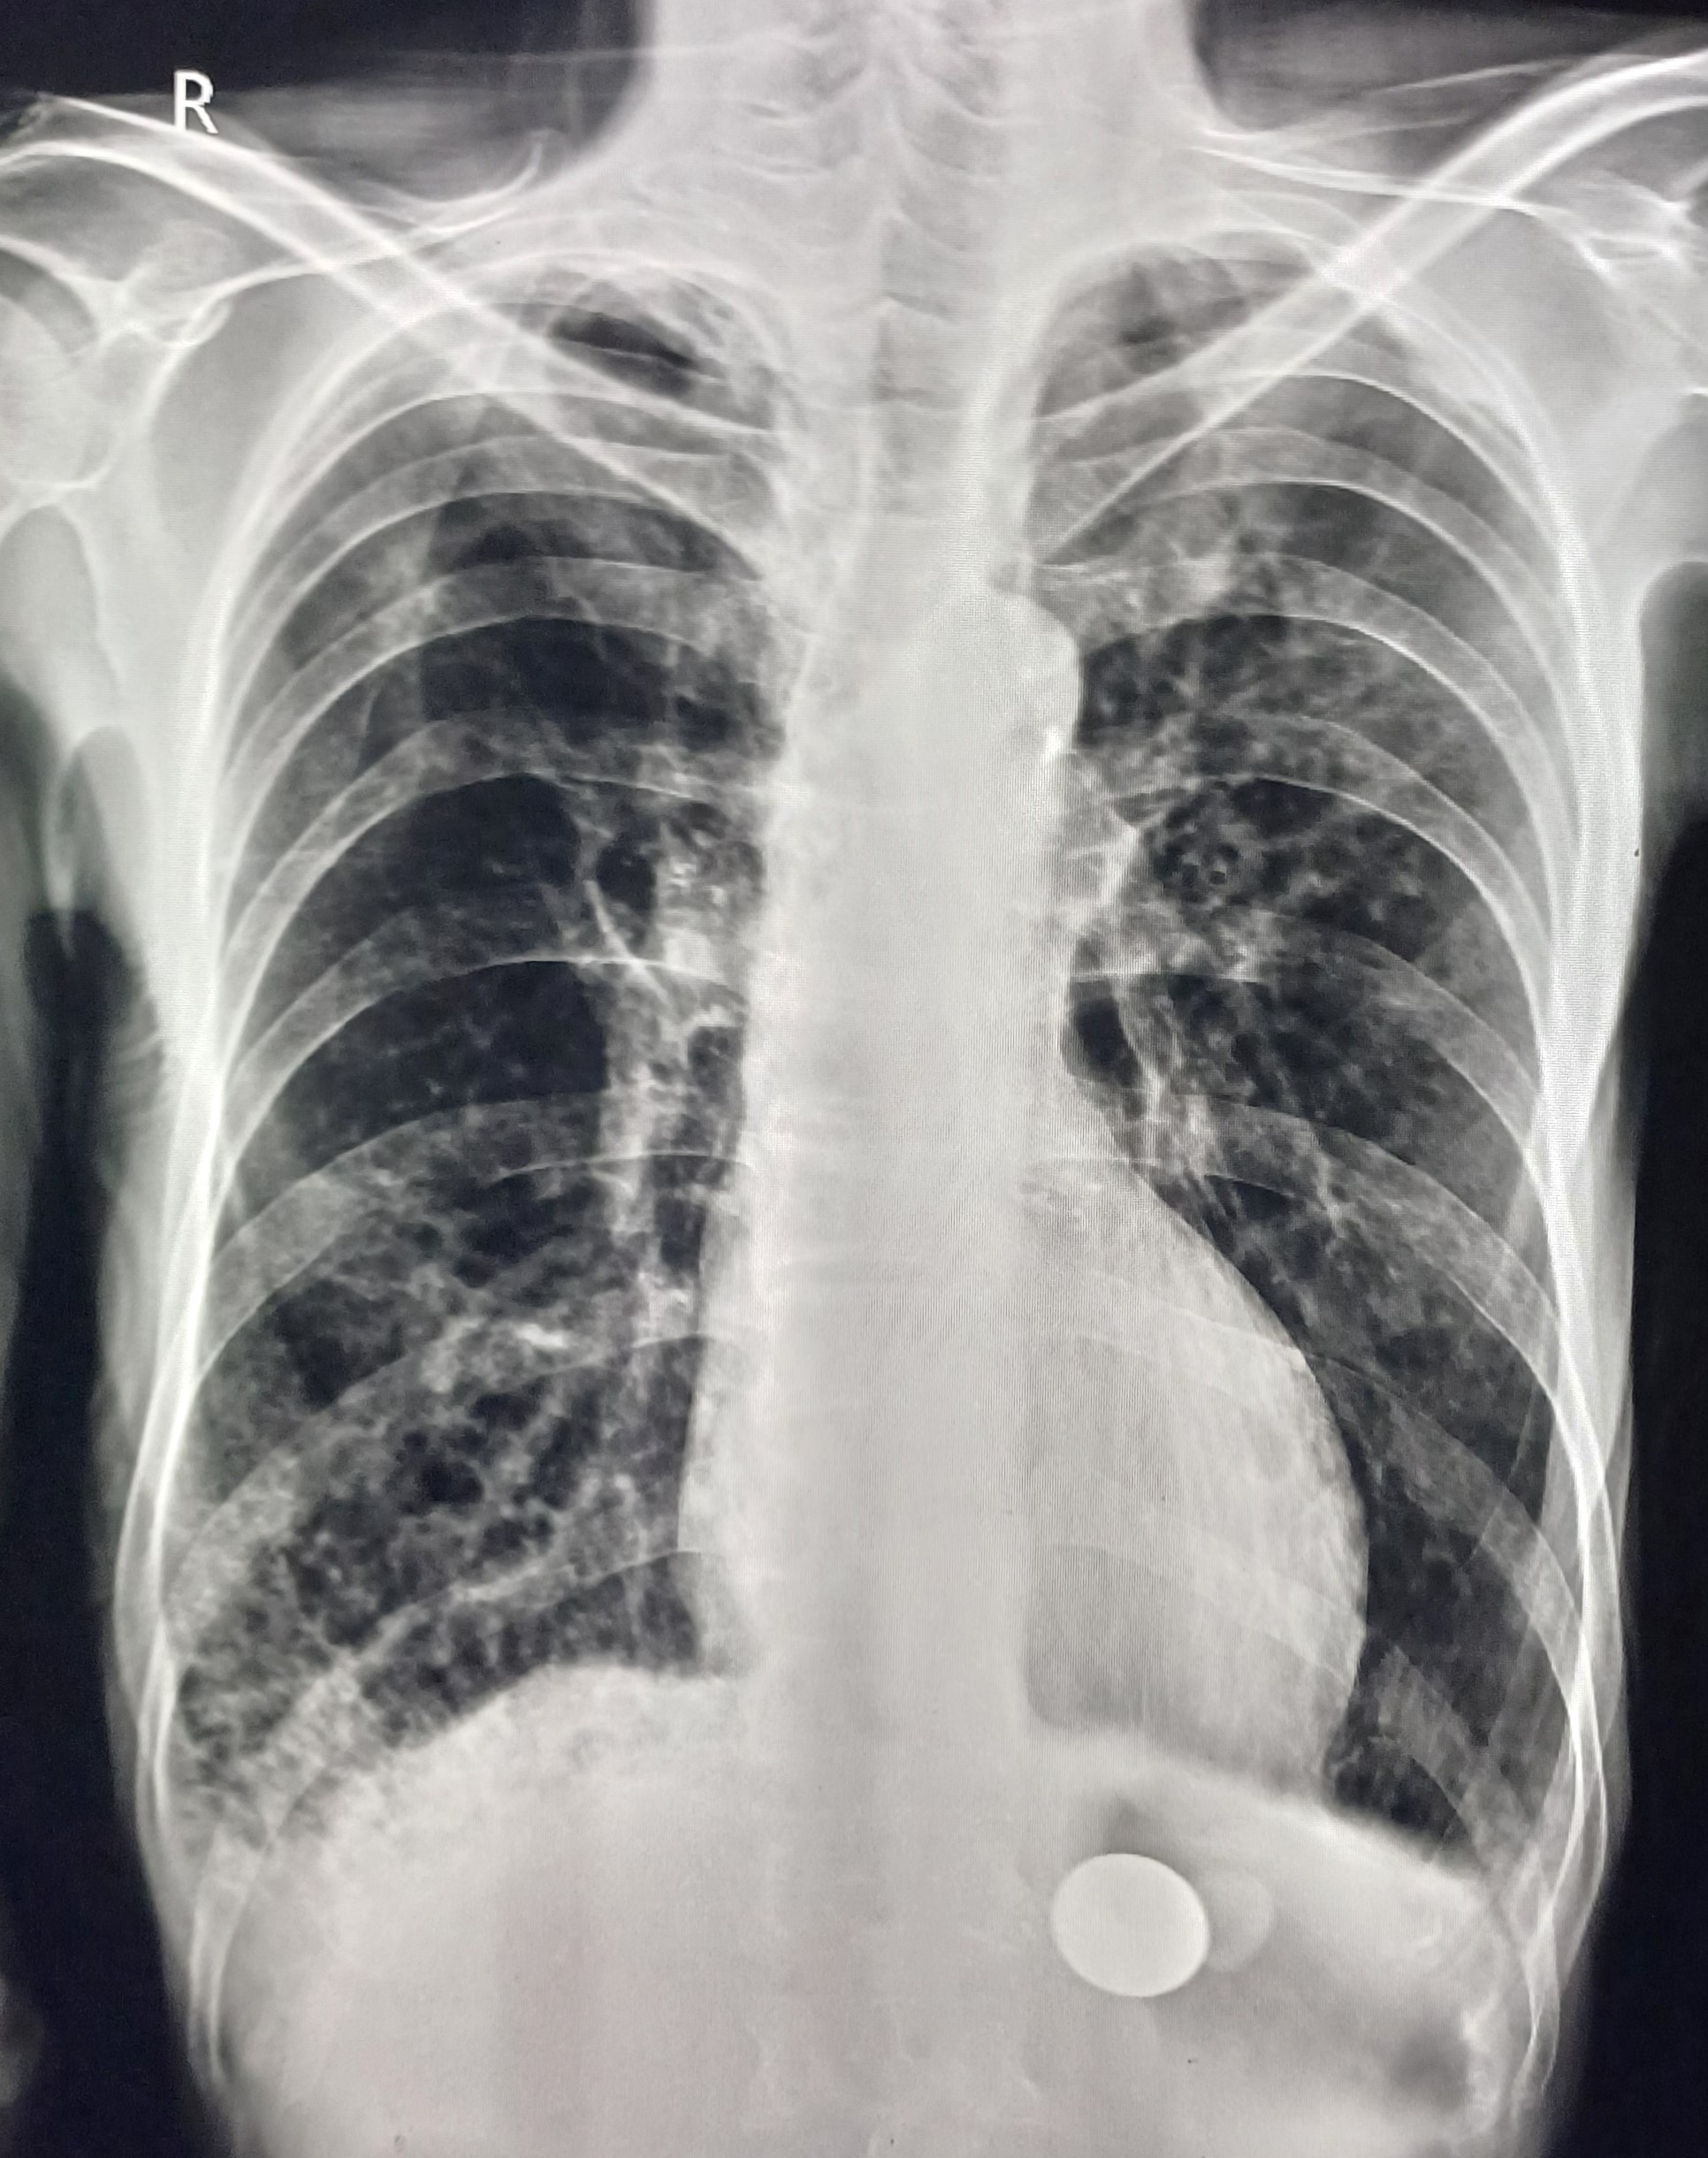

| 4 | IGGMC, Nagpur, Nagpur | P2 | 29-4468 | Moh. Salehuddin | Consent taken on Paper | 68 Yrs. |

Provisional Diag : Miliary TB?

Final Diag : Miliary TB |

TB Case (Confirmed) | Bilateral Infiltrate Query Miliary | Abnormality visible on x-ray |

View |

|||